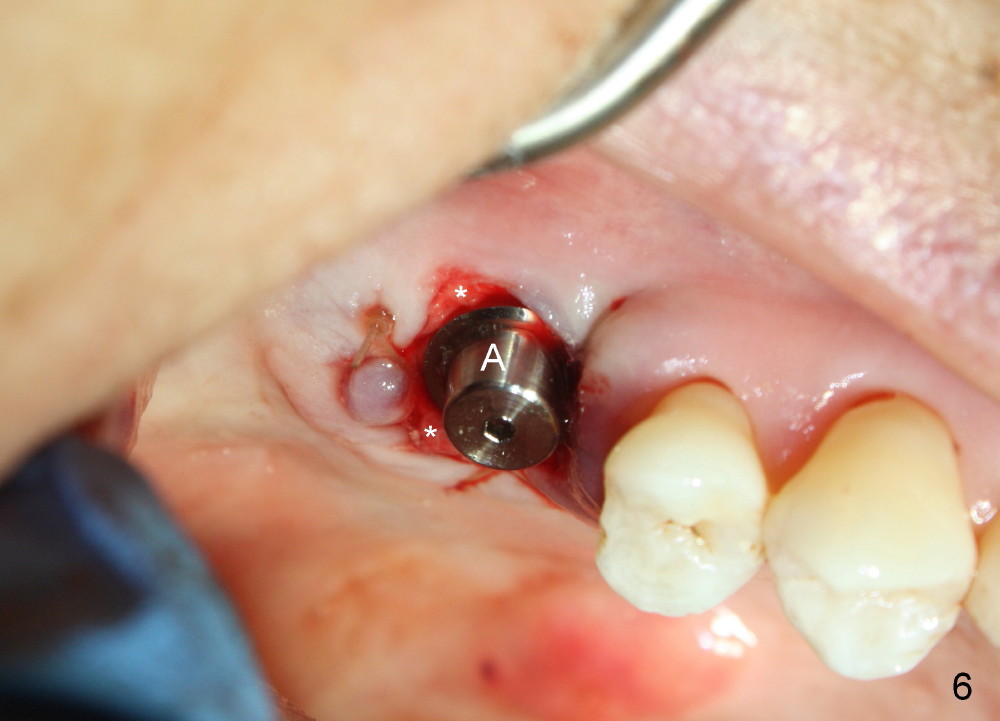

The upper right 1st molar fractures, the lingual portion mobile (Fig.1). There are deep pockets mesiolingually and distolingually. Fig.2 is preop PA, showing mesial bone resorption (*). The 84-year-old lady agrees extraction and immediate implant. Extraction is difficult due to not only root fracture but also hemorrhage. Following debridement of granulation tissue, the 3 sockets are packed with gauze for hemostasis. Even so, there is oozing from the bone. The septum can not be seen clearly. Its position is determined by an explorer. Osteotomes have to be used for osteotomy in the septum, followed by taps. The first intraop PA shows that 5x20 mm tap penetrates the sinus floor (Fig.3 ^). The osteotomy is further enlarged until 7x17 mm tap with stability (Fig.4). So far there has been no sign of sinus membrane perforation. Mixture of freeze dry mineralized bone and Osteogen is placed in the socket and pushed to the buccal and lingual walls as well as into sinus using a 4 mm flat end osteotome. A 7x17 mm implant is initially difficult to be inserted possibly due to blockage by bone graft. The osteotomy have to be recreated by a series of osteotomes and taps before placement of the 7x17 mm implant. It appears that the apical threads have been engaged into the sinus floor for primary stability (Fig.5). The insertion torque is 40 Ncm. According to our experience (1,2), this is not enough; finally the torque is increased to 60 Ncm by turning the implant more apically. The large implant obliterates the socket mesiodistally; the buccal and lingual gaps are filled with bone graft, followed by a collagen membrane (Fig.6 *) and suture. In order to protect the membrane, a short abutment is placed (A) and perio dressing (Fig.7*) is placed without occlusal interference. The abutment is removed 1 month postop, as the perio dressing has been dislodged. The patient returns for restoration 8 month postop. Bone regeneration occurs apparently in the coronal aspect of the implant (Fig.8), especially mesially (*, as compared to Fig.5). The gingiva-level implant is slightly subgingival mesially (Fig.9 M), probably due to high placement (compare to Fig.6). There is no bone resorption 6 months post crown (Fig.10 C) cementation.